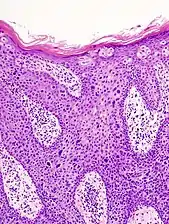

Histopathologically, the epidermis in SCC in situ (Bowen’s disease) will show hyperkeratosis and parakeratosis. There will also be marked acanthosis with elongation and thickening of the rete ridges. These changes will overly keratinocytic cells which are often highly atypical and may in fact have a more unusual appearance than invasive SCC. The atypia spans the full thickness of the epidermis, with the keratinocytes demonstrating intense mitotic activity, pleomorphism, and greatly enlarged nuclei. They will also show a loss of maturity and polarity, giving the epidermis a disordered or “windblown” appearance.

Two types of multinucleated cells may be seen: the first will present as a multinucleated giant cell, and the second will appear as a dyskeratotic cell engulfed in the cytoplasm of a keratinocyte. Occasionally, cells of the upper epidermis will undergo vacuolization, demonstrating an abundant and strongly eosinophilic cytoplasm. There may be a mild to moderate lymphohistiocytic infiltrate detected in the upper dermis.[33]

Bowen's disease is essentially equivalent to and used interchangeably with SCC in situ, when not having invaded through the basement membrane.[33] Depending on source, it is classified as precancerous[34] or SCC in situ (technically cancerous but non-invasive).[35][36] In SCC in situ (Bowen's disease), atypical squamous cells proliferate through the whole thickness of the epidermis.[33] The entire tumor is confined to the epidermis and does not invade into the dermis.[33] The cells are often highly atypical under the microscope, and may in fact look more unusual than the cells of some invasive squamous cell carcinomas.[33]